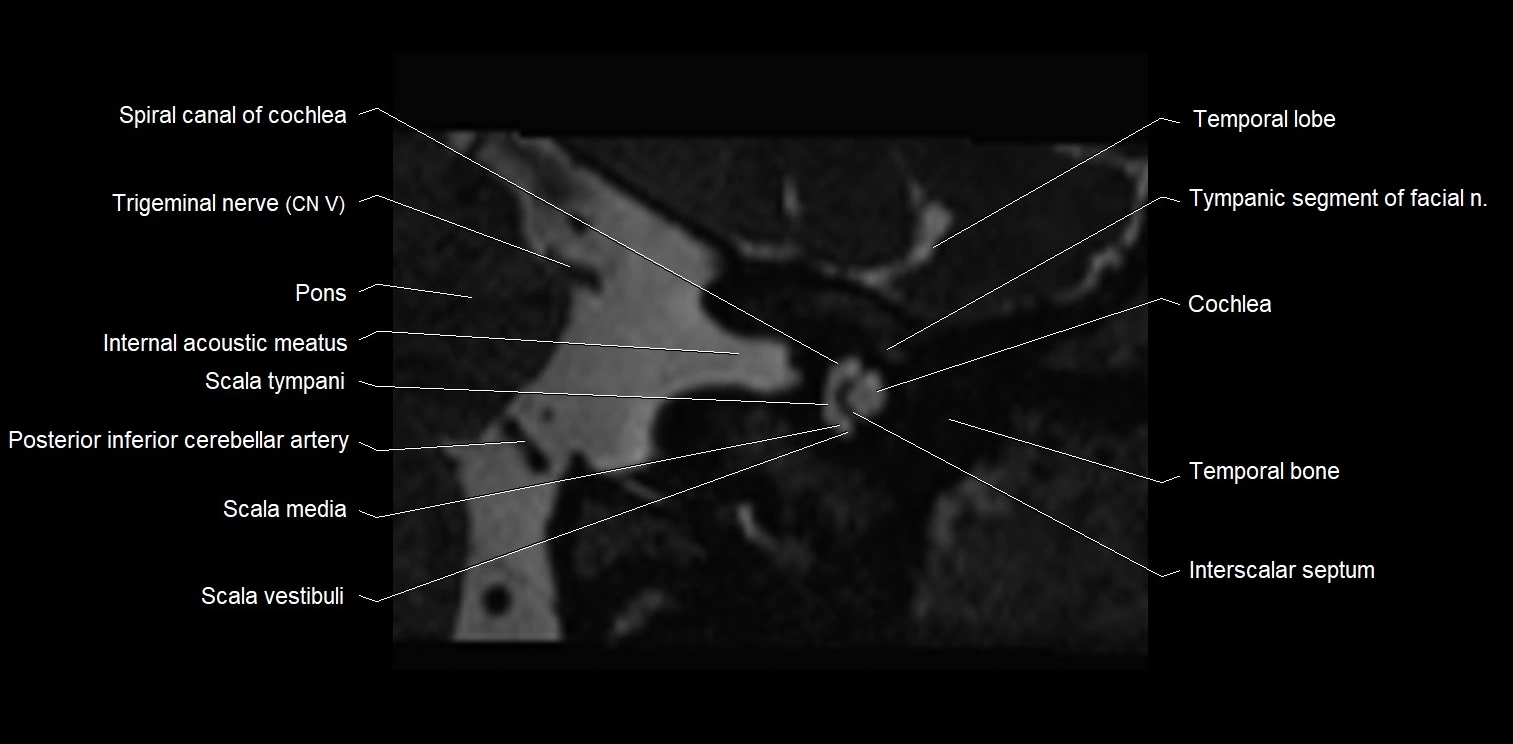

MRI images

image